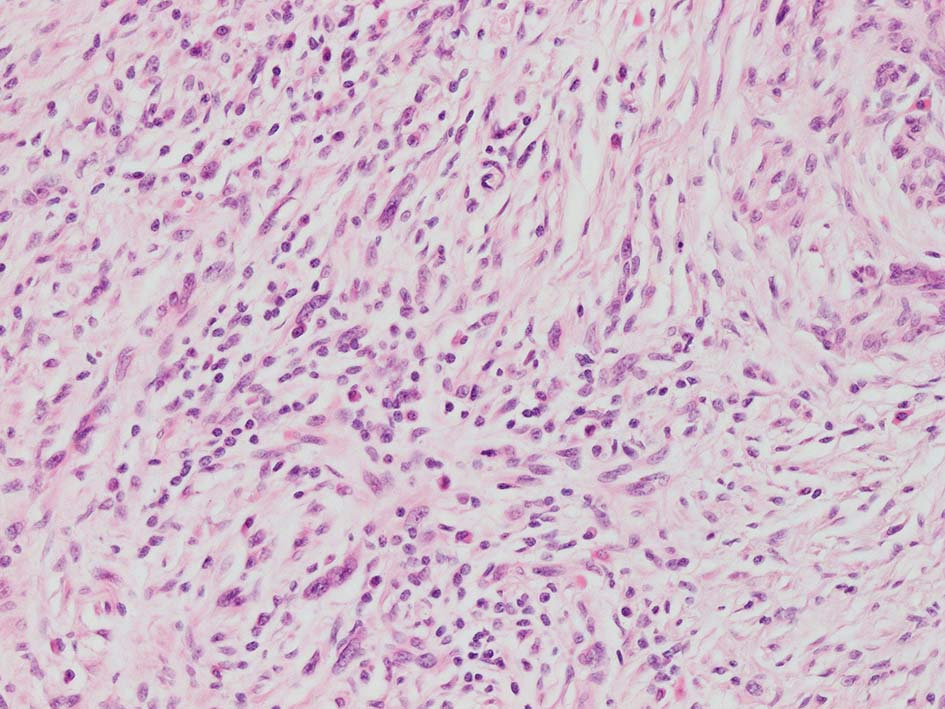

紡錘形異型メラノサイトが著明な間質反応(desmoplasia)を伴い増殖する特殊な色素性病変。*1. desmoplastic neurotropic melanomaは, desmoplastic melanomaのうち神経向性(neurotropism:神経周囲侵襲像)がめだつものでReedら*2が最初に報告した。

いずれも腫瘍細胞の異型性が乏しく, 背景の間質反応がめだつこと, メラニンの存在が目立たないことが特徴である。

リンパ濾胞が細血管周囲に形成され, この部分に異型といえる細胞が増加している(S100+)